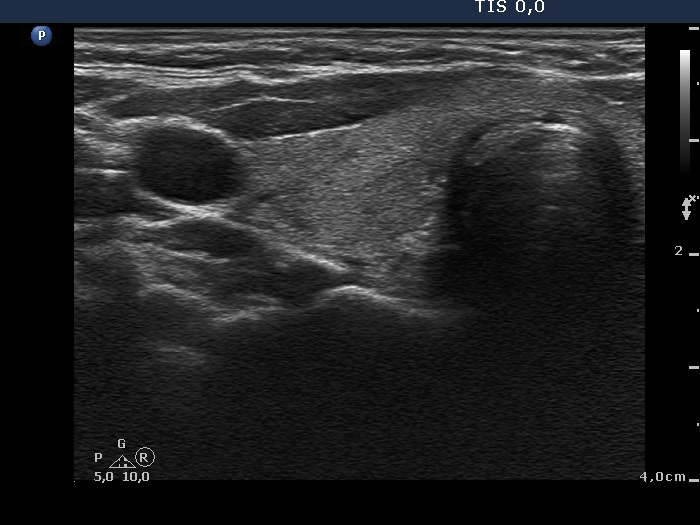

Initial examination (first row of images):

Clinical presentation: A 39-year-old woman was referred for evaluation of neck complaints lasting for more than a month. The patient had fever, neck pain. She has got two courses of antibiotics and non-steroid anti inflammatory drugs which had no effect.

Palpation: The right lobe was painful and hard while the left lobe was tender.

Laboratory examination: TSH 0.01 mIU/L, FT4 29.1 pM/L, FT3 7.45 pM/L, CRP 31.2 mg/L.

Ultrasonography: The thyroid presented with hypoechoic areas which had blurred borders. The echogenicity index was approximately 65% in the right and 20% in the left lobe. The thyroid was almost completely avascular.

Diagnosis: subacute, granulomatous de Quervain's thyroiditis.